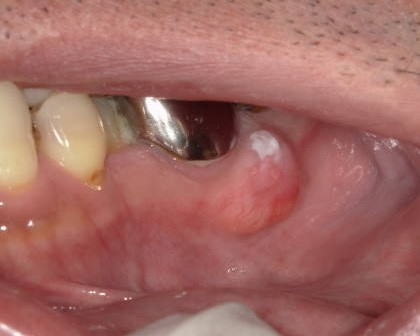

症例

症例2:すでに悪性化していた症例